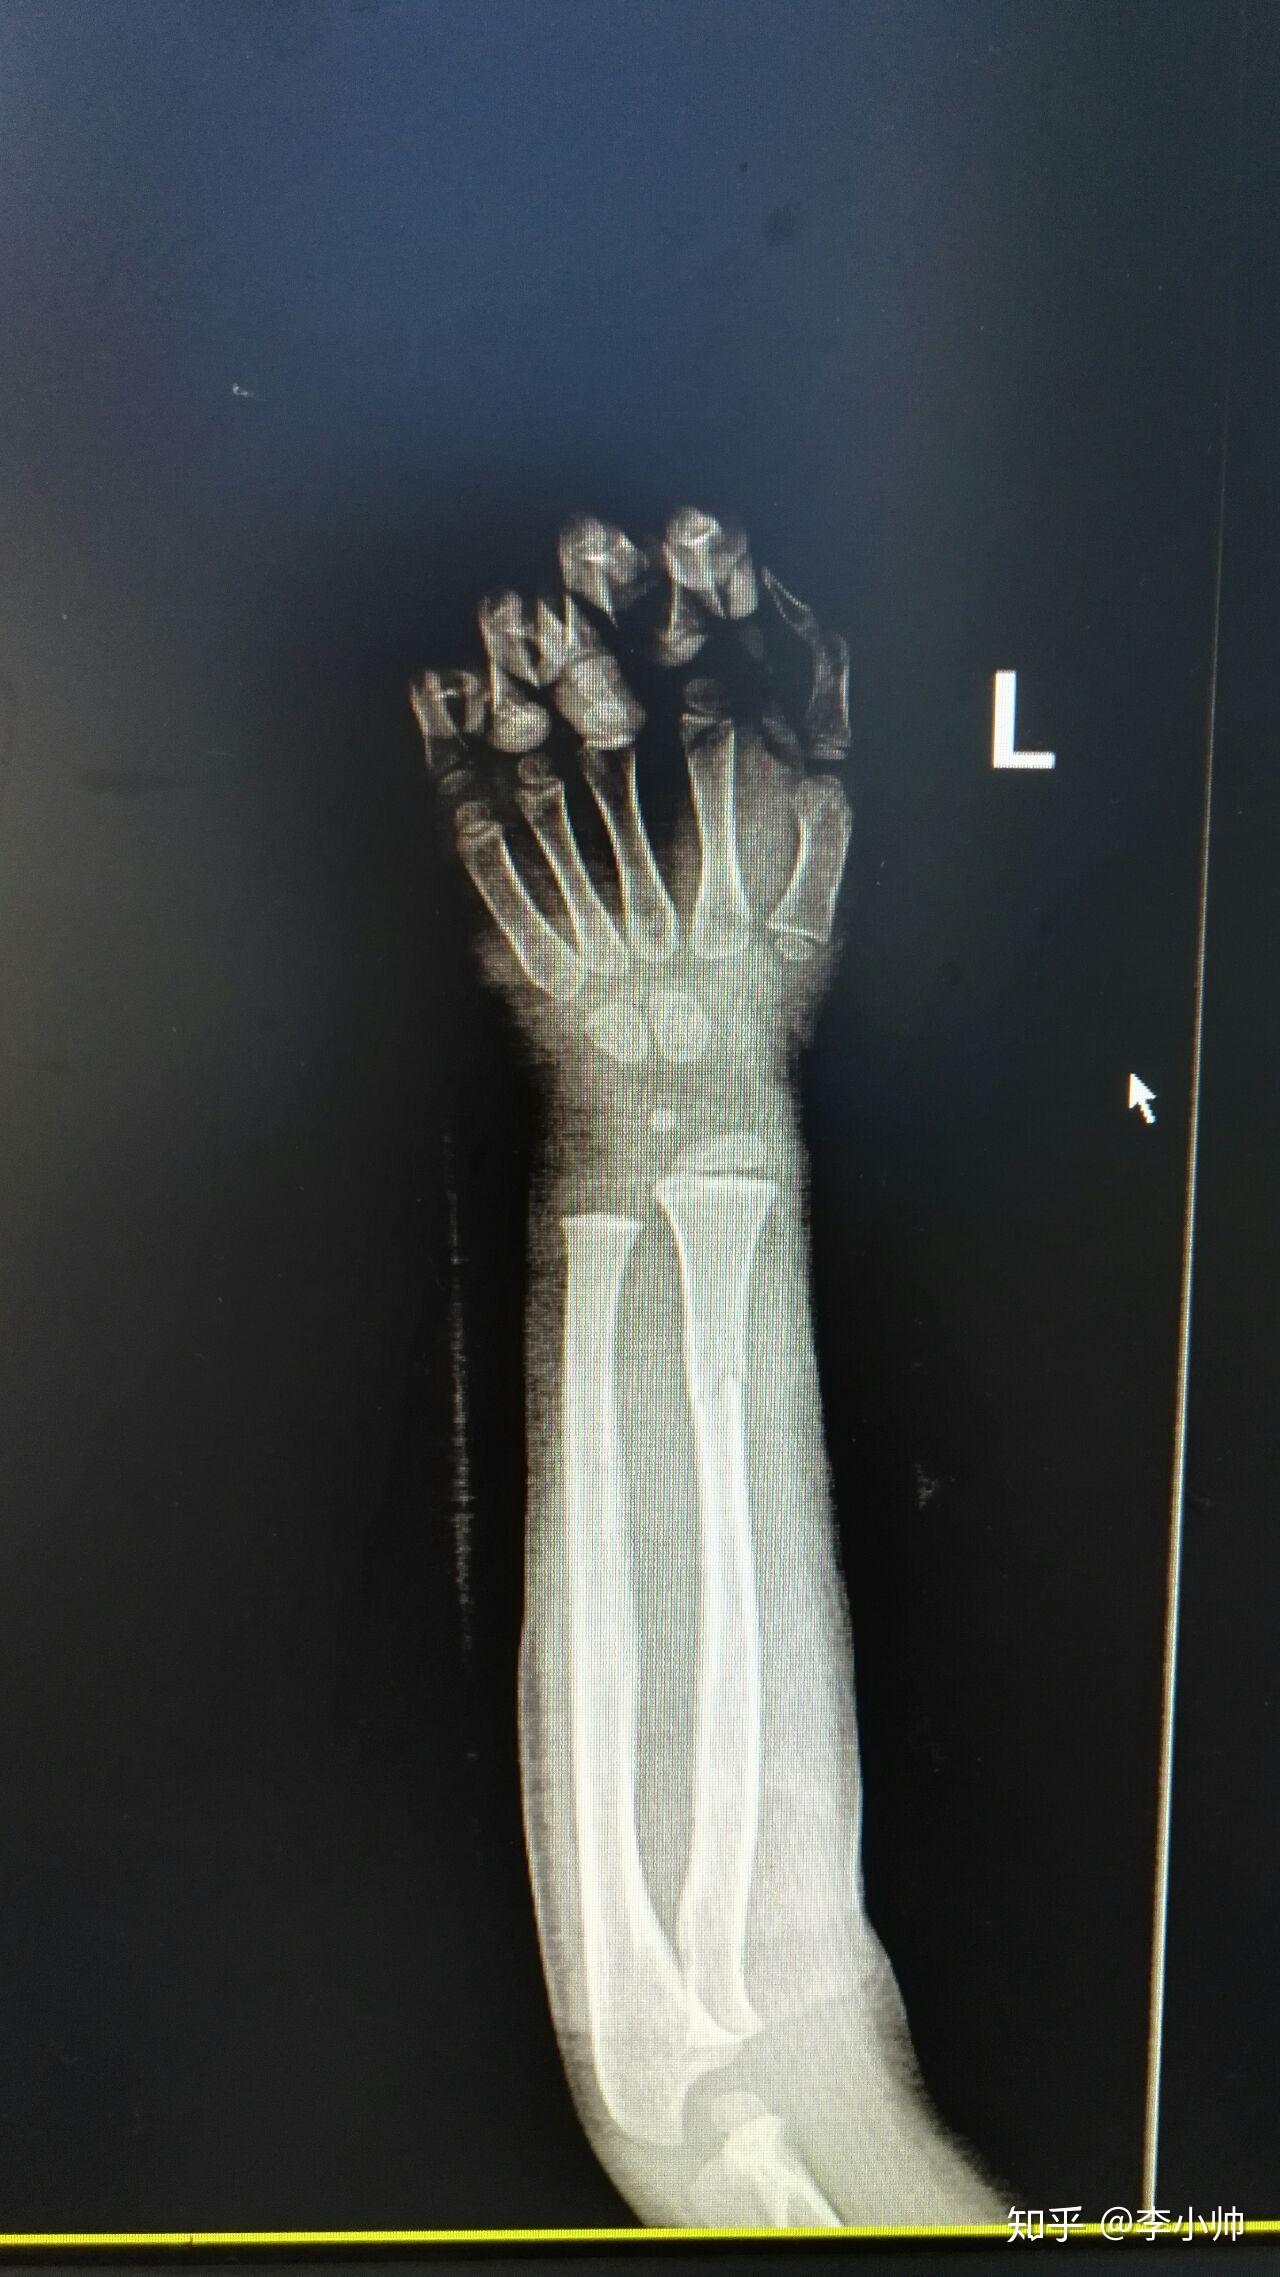

14岁胫腓骨远端骨折闭合复位外固定架固定手术一例

图片尺寸1948x3284